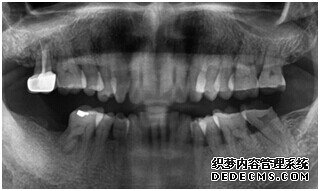

由CT片检查来看,刘女士口腔健康环境还是很好的,牙槽骨也适合种植牙的条件,而且由我们最后一颗牙是非常重要的,经过专家的建议和详细解释了原因之后,刘女士选择了美国百康种植牙。

成功植入种植体后的效果图

种植体成功植入后的CT效果图